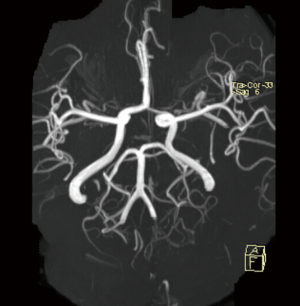

Routine laboratory tests were unremarkable, including liver and renal function, thyroid function, immunologic tests and serum ceruloplasmin level. The exception was a slightly elevated fasting serum glucose level (125 mg/dL). Transthoracic echocardiography was normal, and 24-hour Holter monitoring did not show arrhythmia. Subsequent brain magnetic resonance imaging at 3.0 T revealed acute ischemic stroke involving the left putamen (Figure 2) and periventricular area. However, magnetic resonance angiography did not show any stenosis in the left middle cerebral artery (Figure 3). Diffusion tensor imaging of the brainstem and cervical spine revealed normal cortico-spinal tract decussation in the lower medulla oblongata (Figure 4). The patient was diagnosed with acute onset post-stroke hemiballism that induced MM in her unaffected limb. She was given one week of clonazepam and haloperidol therapy, after which MMs and hemiballism nearly disappeared (Figure 5). The patient was discharged with standard ischemic stroke prevention measures including aspirin and atorvastatin. At follow-up 1 year later, no further episodes of involuntary movement had occurred.